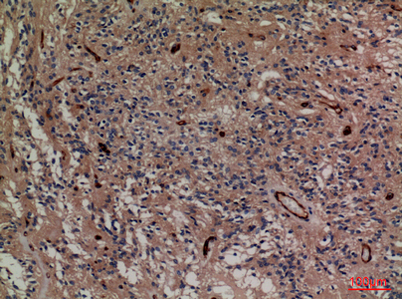

| Dilutions: | Western Blot: 1/500 - 1/2000. IHC-p: 1:100-300 ELISA: 1/20000. Not yet tested in other applications. |